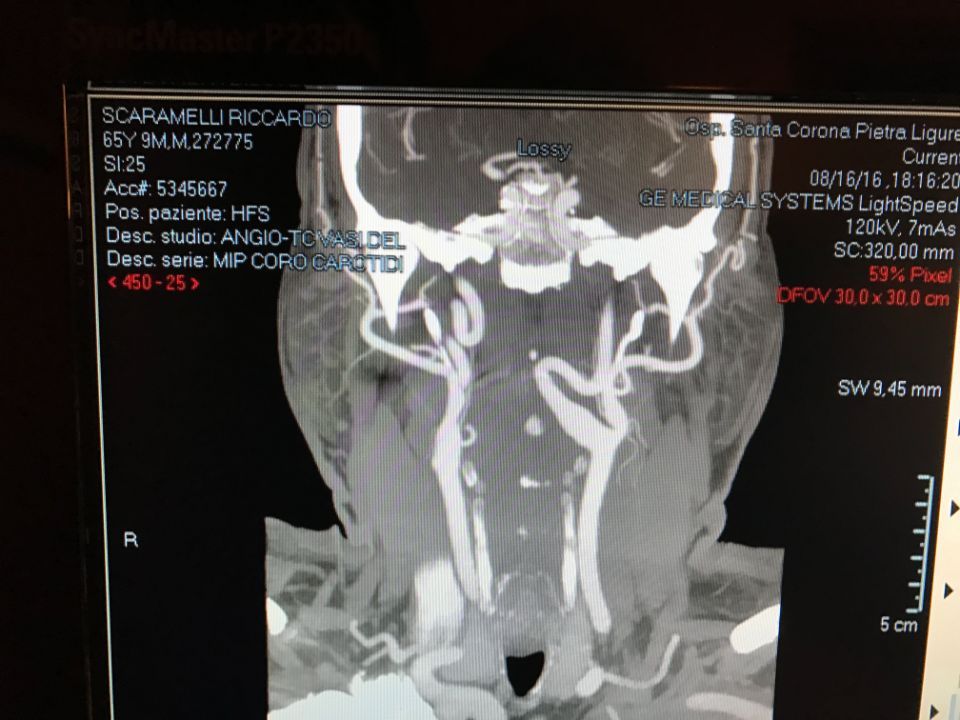

Ecco alcune immagini degli interventi eseguiti dal Dottor Viglione presso il suo studio a Cuneo.